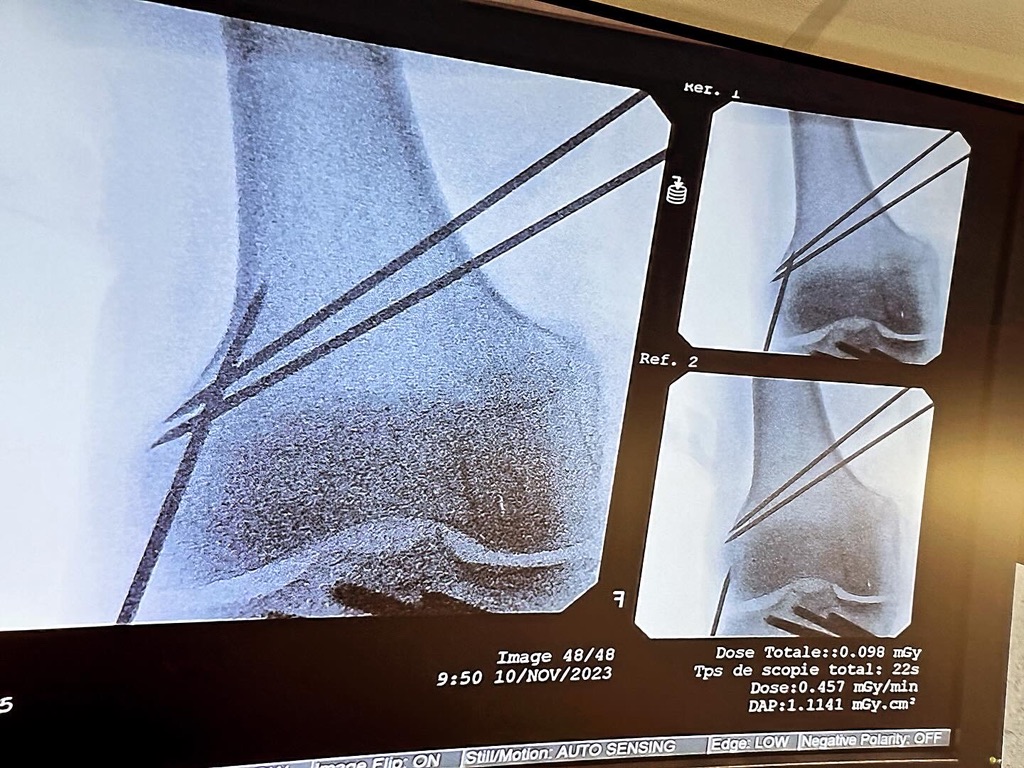

2023年11月にフランスのナントで開催されたESSKA (ヨーロッパスポーツ外傷・膝・関節鏡学会)が主催する膝関節周囲骨切り術の認定医試験 (ESSKA European Certification Programme: Osteotomies around the knees)に整形外科の大西医師が参加しました。以下大西医師のコメントです。

欧州を中心に南米やアフリカからも参加者がおり、アジアからの受講者は私ひとりでしたが、日本の学術集会とは異なる考え方や骨切り術のメッカである、ヨーロッパでの最新の知見に触れることができました。

実技試験は合格でき、当院での膝周囲骨切り術の診療に自信が持てる結果となりました。今春の3月に、最終のオンライン口頭試験がありますが、引き続き精進すると共に、それぞれの患者さんの状態やニーズに合わせた治療ができるように努めて参ります。